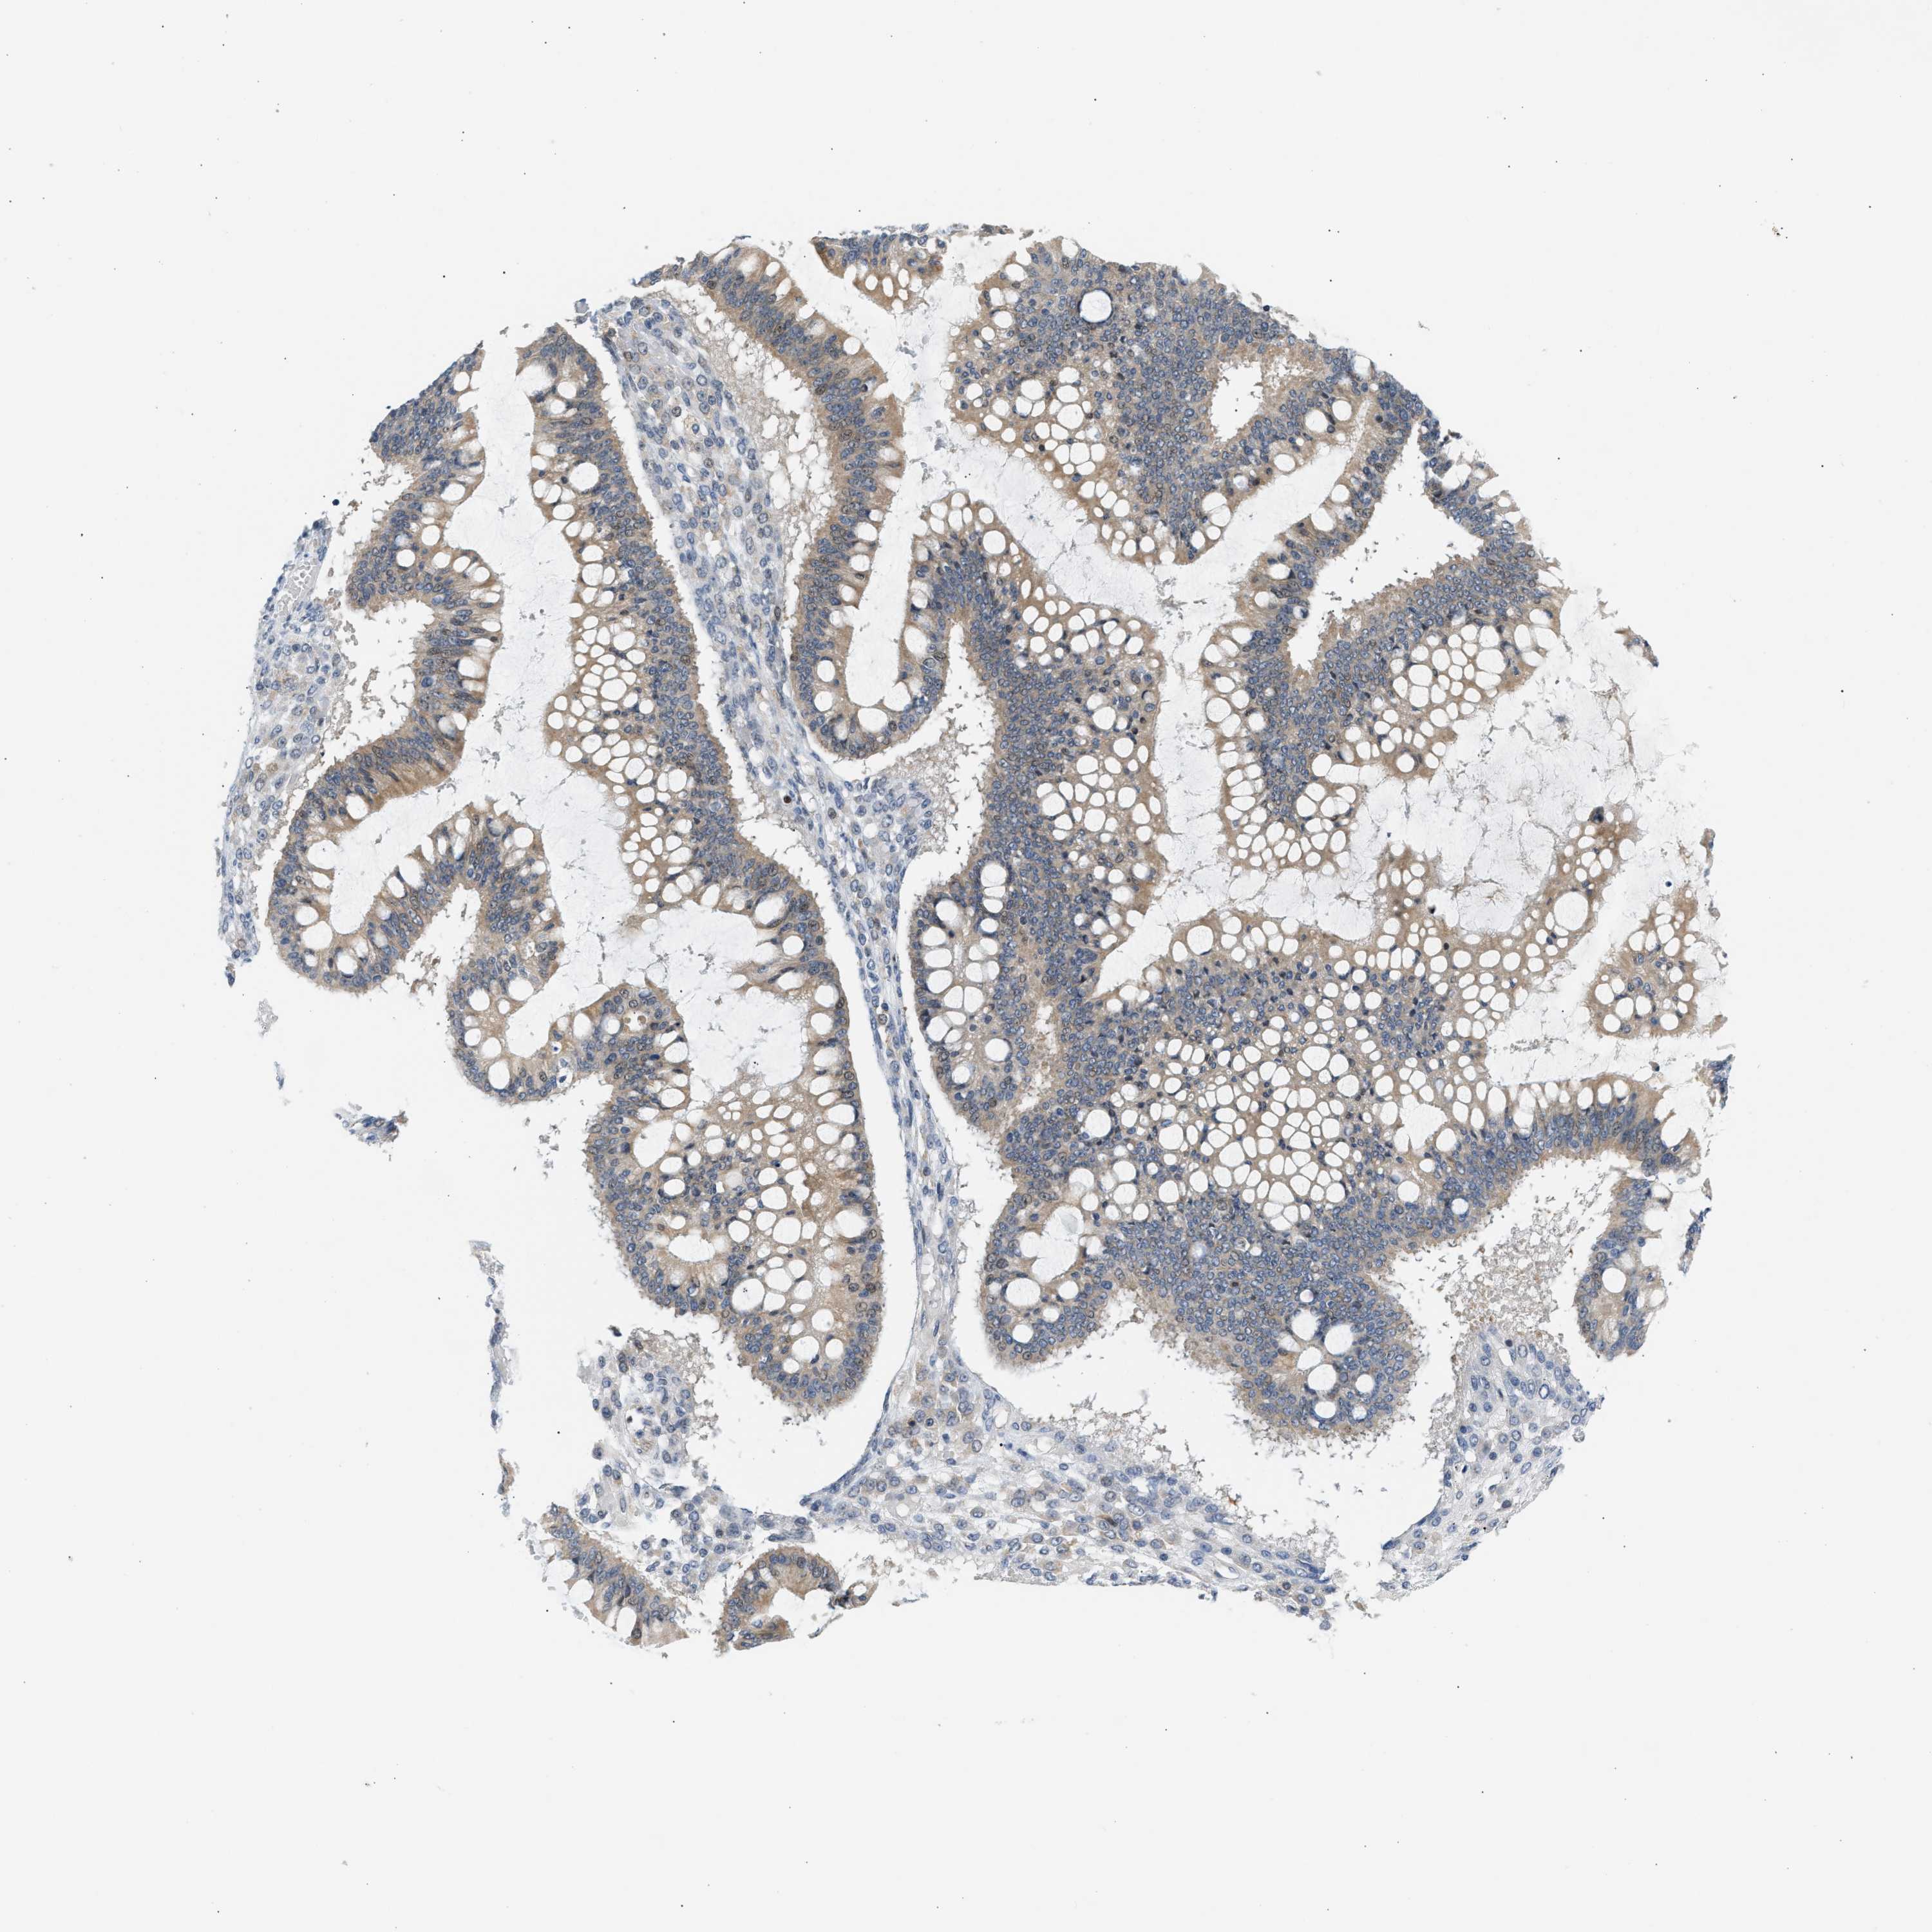

OVARIAN CANCER - Protein expressioni

A mouse-over function shows sample information and annotation data. Click on an image to view it in a full screen mode. Samples can be filtered based on level of antibody staining by selecting one or several of the following categories: high, medium, low and not detected. The assay and annotation is described here.

Note that samples used for immunohistochemistry by the Human Protein Atlas do not correspond to samples in the TCGA dataset.

Antibody stainingi

Antibody staining in the annotated cell types in the current human tissue is reported as not detected, low, medium, or high, based on conventional immunohistochemistry profiling in selected tissues. This score is based on the combination of the staining intensity and fraction of stained cells.

Each image is clickable and will lead to virtual microscopy that enables deeper exploration of all samples and also displays staining intensity scores, fraction scores and subcellular localization as well as patient and tissue information for each sample.

Antibody CAB020139

Staining

High

Medium

Low

Not detected

Intensity

Strong

Moderate

Weak

Negative

Quantity

>75%

75%-25%

<25%

None

Location

Nuclear

Cytoplasmic/membranous

Cytoplasmic/membranous,nuclear

Cystadenocarcinoma, serous, NOS

Carcinoma, endometroid

Cystadenocarcinoma, mucinous, NOS

Carcinoma, NOS